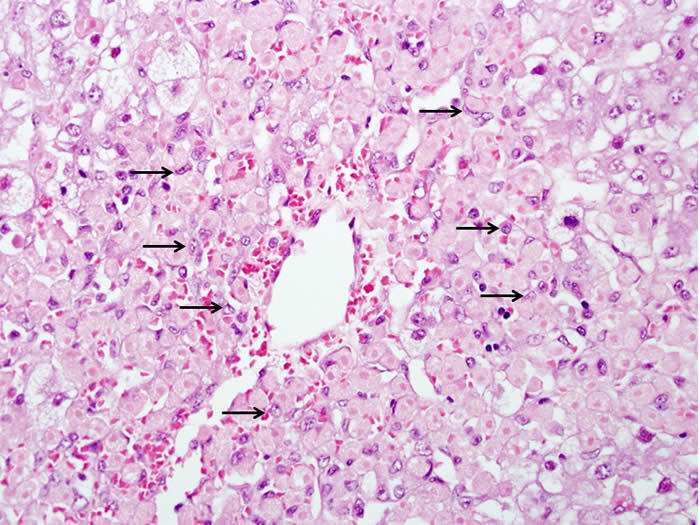

对乙酰氨基酚中毒。汇管区域显示炎症,很可能与先前存在的酒精性肝病有关。肝细胞大部分存活,但坏死区边缘明显(箭头所示)

图片6.png

少数存活肝细胞留在静脉附近,但大多数以肝细胞鬼影的形式出现。巨噬细胞(箭头)已经渗透到坏死区。坏死边缘的肝细胞显示气球样损伤和脂肪变性。